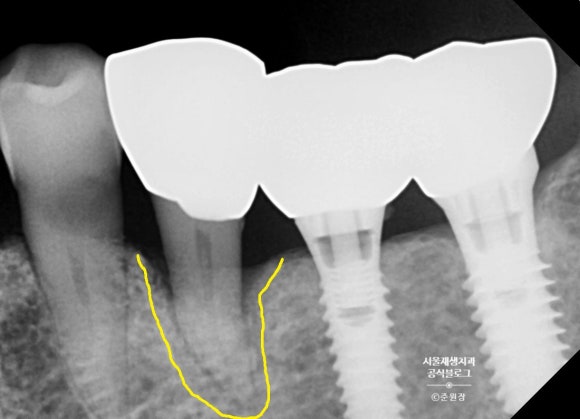

증명사진을 살펴보겠습니다.

치아 뿌리의 외형을 따라 잇몸뼈들이 녹아있는 소견입니다.

당연하게도 치아는 몹시도 흔들리고 있었구요.

치주탐침 검사로 골소실 정도를 파악해보니, 이미 뿌리 끝까지 뼈가 녹아내려 더 이상 손 쓸 수가 없는 상황이었습니다.

조금만 더 일찍 오셨더라면...!